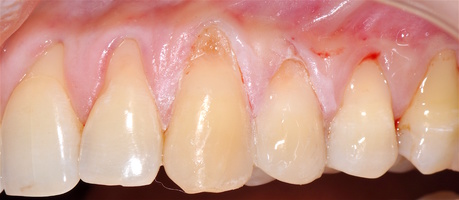

Во всех случаях применения аутотрансплантата и ТМО (dura mater) наблюдается сопоставимый положительный клинический результат по всем параметрам оценки рецессий десны (табл. 4). В случае нескольких зубов в области наиболее глубоких рецессий с наименьшими клиническими показателями имеет место сохранение класса рецессии не более первого класса (9 зубов) и глубиной не более 2 мм, 1.6 зуб — 3 мм.

В зарубежной литературе встречается также совокупный показатель эффективности лечения рецессий десны — процент закрытия корня зуба — отношение разница между конечным и исходным значениями глубины рецессии к исходному значению в процентах. Положительный результатом лечения является значение равное или более 80% [4]. Использование только показателя глубины рецессии десны для анализа эффективности лечения без учета остальных показателей (ТКД, ШКД, РРД, ЗДК) не дает полной картины результата и может быть применимо только в совокупности с другими показателями (рис. 6а-й).

Так в нашем случае процент закрытия корня зуба наблюдается больше 80% у 13 зубов. Менее 80% — у 11 зубов. Это связано с сохранением класса рецессии после лечения в области зубов с наибольшим классом рецессии и наибольшим показателем глубины рецессии. При этом средний показатель всех 24-х оперированных зубов — 83,1%. При этом среднее значение процента закрытия корня зуба для зубов с положительным результатом (более 80%) составляет 96,65%. Среднее значение для результатов менее 80% — 54,73, что связано с изменением глубины рецессий с 6 мм до 3 мм, с 4 мм до 2 мм и с 2 до 1 мм. При этом для аутотрансплантата и для ТМО результаты сопоставимы.